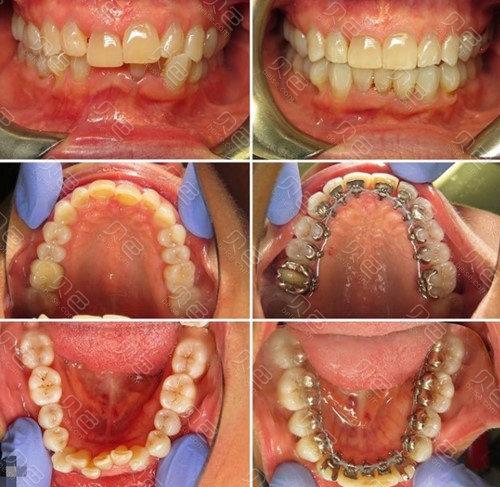

服务流程上,医院推行“首诊负责制”与“全程管理”模式,患者初诊时,医生会进行全面的口腔检查(包括口腔卫生、牙周状况、颞下颌关节等),拍摄X线片(根尖片、曲面断层片,必要时加拍CBCT),取研究模型,并记录面部及口内照片,随后通过多学科会诊(如涉及正颌外科、修复科等复杂病例),确定最终治疗方案并详细沟通治疗周期、费用及预期效果,治疗过程中,患者需定期复诊(一般4-6周一次),医生会根据牙齿移动情况调整矫治力,全程监控牙齿移动速度与颌骨变化,矫正结束后,进入保持阶段,医生会根据患者情况制作保持器(如Hawley保持器、透明压膜保持器等),并指导佩戴方法及随访计划,防止复发。